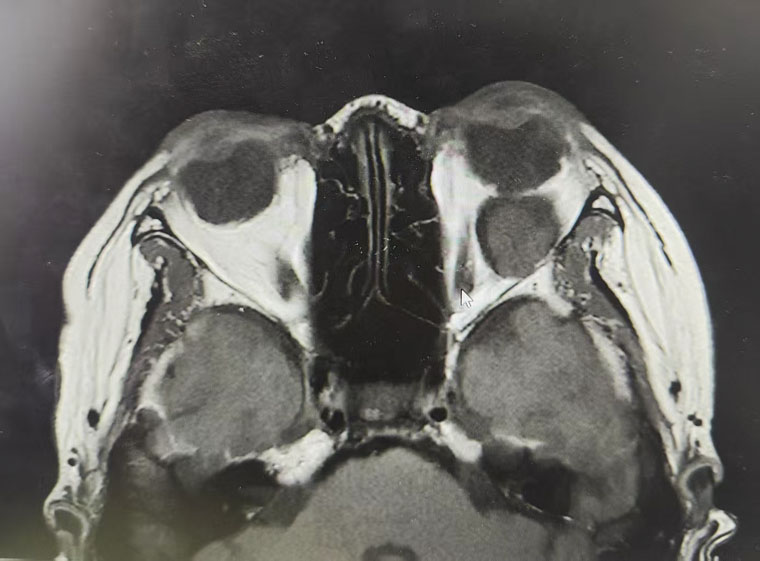

该患者因“发现右眼眼球逐渐突出2年”就诊于我院,眼眶CT检查显示,眼球正后方隐藏着一个与眼球等大的肿物,占位效应明显。眼球后方空间狭小、结构精密,如何在这一关键区域将体积较大的肿瘤完整剥离,同时保护视神经、眼外肌等重要解剖结构不受损伤,加之患者明确要求面部不能留下疤痕,这些因素均对手术精准度与微创性提出了极致挑战。

术前

术后